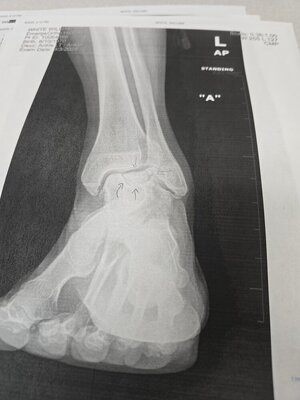

25 years ago I was in a bad car crash. At the time, after x-rays, the doctor said I just had a bad sprain. Fast forward to today when I had X-rays done, and the doctor said it actually was broken 25 years ago, and healed poorly. Now I'm looking at having a fused or replaced.